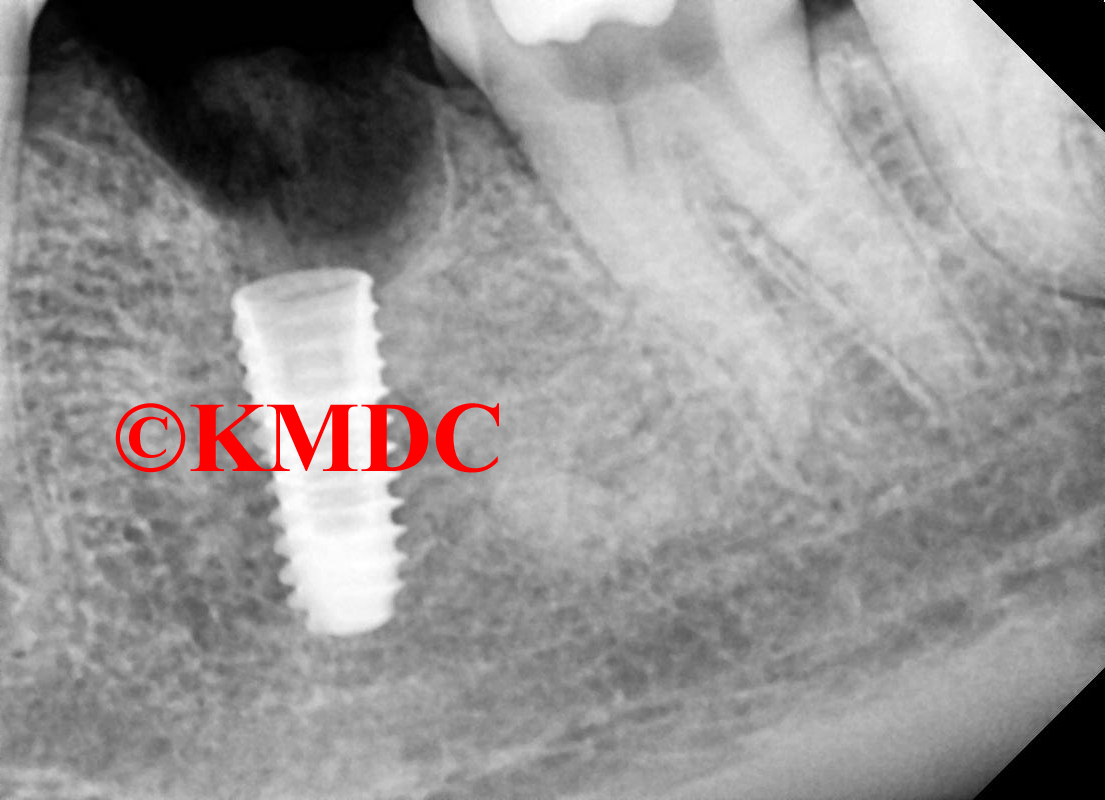

Clinical Gallery